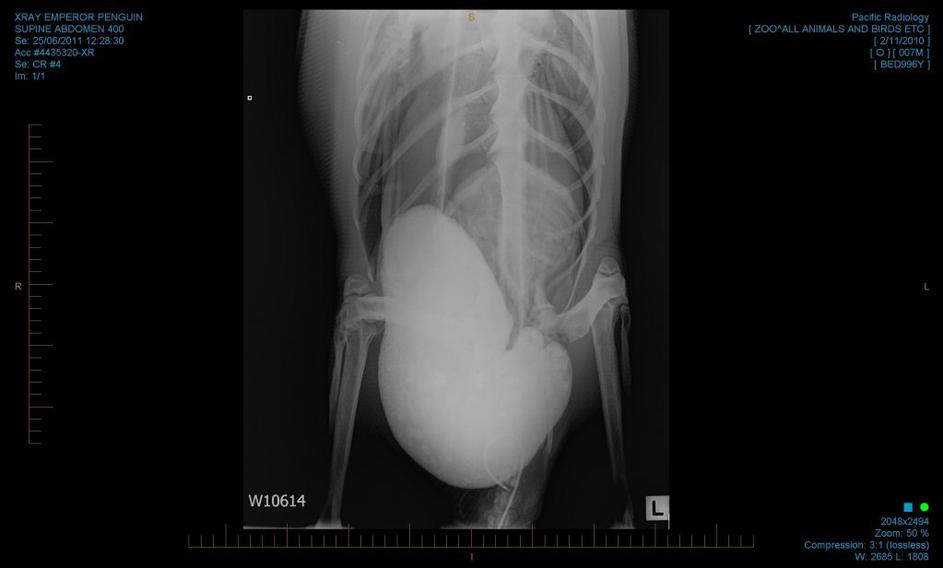

pingvin, operacija, Nova Zelandija, endoskopija Rentgenski posnetek želodca cesarskega pingvina. EPA pingvin, operacija, Nova Zelandija, endoskopija